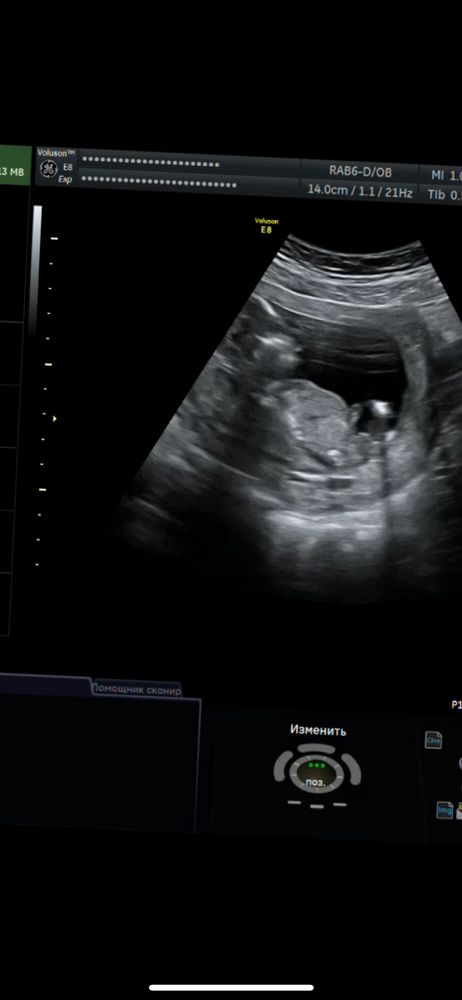

Мальчик или девочка

между ног пуповина, как на первом так и на втором фото, так что можно и ошибиться

Elizaveta, а второе фото не то ?

Наталья, не увидела второе похоже на мальчика

У кого ошибались с полом на 15 неделях беременности Сроки определения пола в инвитро